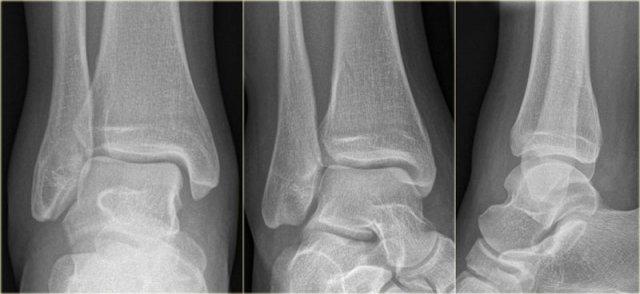

Đây là hình ảnh của một ca bệnh cực kỳ khó.

Bệnh nhân nữ bị bong gân cổ chân và đau cả hai bên trong và ngoài.

Bệnh nhân được bác sĩ đa khoa chuyển đến khoa Chẩn đoán Hình ảnh.

Kỹ thuật viên chụp các tư thế chuẩn gồm thẳng (AP), Mortise và nghiêng, sau đó trình bày cho bác sĩ X-quang, người đã khá băn khoăn khi đọc phim.

Hãy đọc hình ảnh trước, sau đó tiếp tục đọc phần giải thích.

Các dấu hiệu bao gồm:

-

Phù nề phần mềm cả hai bên trong và ngoài (mũi tên đỏ).

Đặc biệt, phù nề phía trong nên gợi ý khả năng chấn thương xoay ngoài – sấp (Weber C). - Đường thấu quang trên tư thế Mortise (mũi tên đen) và tư thế nghiêng. Dấu hiệu này nên gợi ý gãy tertius.